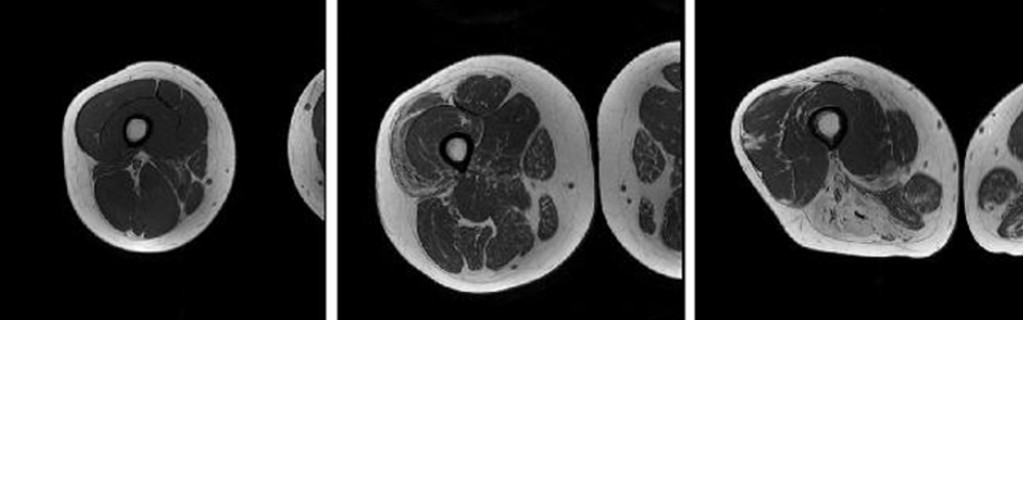

We use in vivo imaging and spectroscopy methods to advance the quantitative understanding of human physiology and pathophysiology. We are particularly interested in learning about the structure and function of skeletal muscle and other metabolically important organs, such as the liver and brown adipose tissue. We develop new experimental approaches for studying these organs, and we conduct applied and translational physiology studies that help us to understand how the structure and function of these organs are altered in neuromuscular and metabolic disorders. You can learn more about these projects on the “What We Study” page.